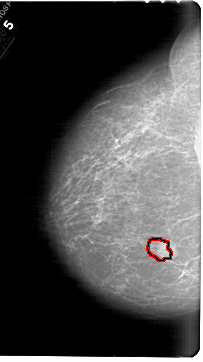

FILE: A_1567_1.LEFT_MLO.OVERLAY TOTAL_ABNORMALITIES 1 ABNORMALITY 1 LESION_TYPE MASS SHAPE LOBULATED MARGINS OBSCURED ASSESSMENT 4 SUBTLETY 4 PATHOLOGY BENIGN TOTAL_OUTLINES 1 BOUNDARY |